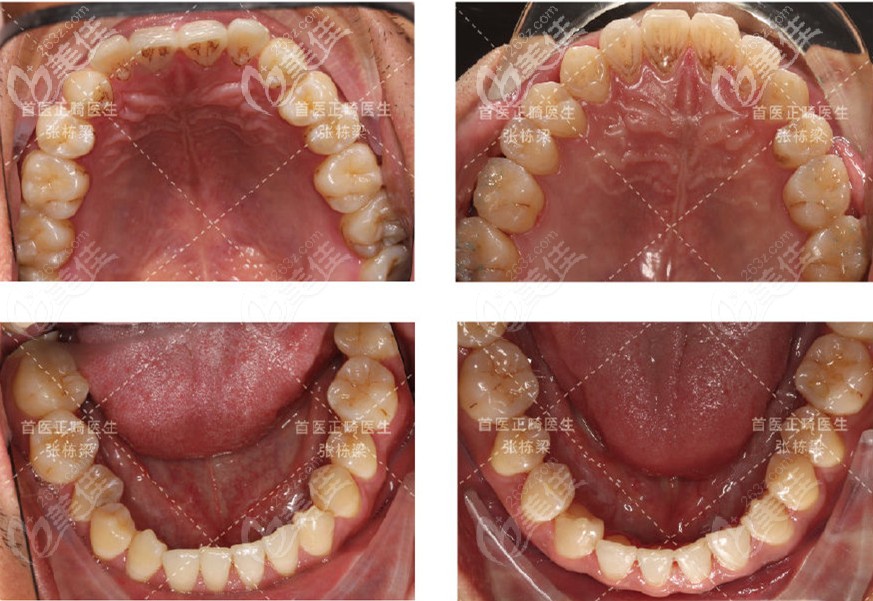

上下颌牙齿都有所改善,且没有牙齿出现脱矿的情况▲